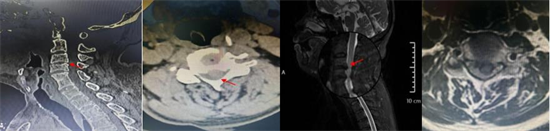

術(shù)前影像資料顯示C3/C4椎間盤突出、極重度頸椎椎管狹窄、C5/6椎體融合

患者李某,70歲,因“四肢乏力、行走不穩(wěn)1年,加重1個(gè)月”入住衡南縣人民醫(yī)院骨科二區(qū),入院檢查診斷為:脊髓型頸椎病、頸椎椎管狹窄癥(C3/C4極重度)、慢性不完全性四肢癱。其中C3/4節(jié)段椎管占位率超過50%以上,脊髓受壓極其嚴(yán)重,若病情繼續(xù)進(jìn)展,可能導(dǎo)致高位截癱甚至呼吸衰竭,危及生命。且李某還存在C5、6節(jié)段先天性融合,短頸畸形,進(jìn)一步增加了術(shù)中暴露和置釘?shù)碾y度,對(duì)主刀醫(yī)生的經(jīng)驗(yàn)、技術(shù)及團(tuán)隊(duì)配合要求極高。